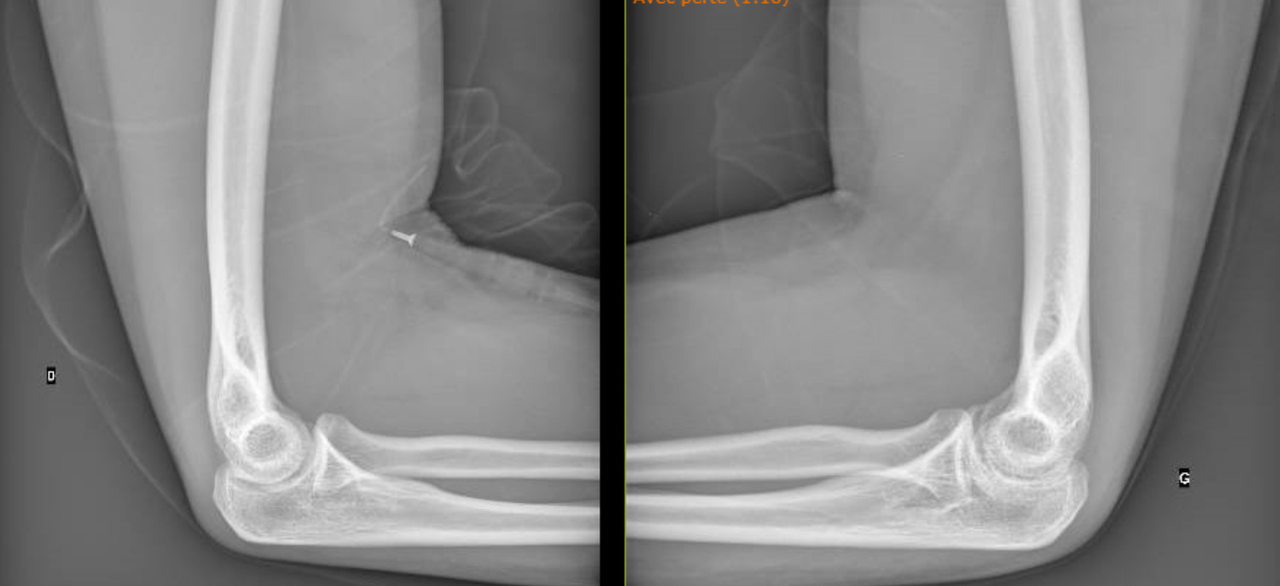

Vous la revoyez quatre mois après la fin de l’antibiothérapie avec des radiographies de contrôle (fig. 3 et 4).

Figure 3 (Source Salomé Abdellaoui, La Revue du Praticien)

Figure 4 (Source Salomé Abdellaoui, La Revue du Praticien)

Elle garde un flessum du coude gauche à 5°, irréductible, qui n’a pas de retentissement fonctionnel.

On voit sur les radiographies que l’articulation est abîmée avec un pincement articulaire à gauche, il y a donc peu de chance que le flessum récupère totalement.

Il n’y pas de douleur ou de retentissement fonctionnel associé au flessum de coude donc pas d’indication actuelle à une prise en charge chirurgicale. En revanche, l’articulation va probablement évoluer vers une arthrose précoce et possiblement vers la mise en place d’une prothèse dans un second temps.